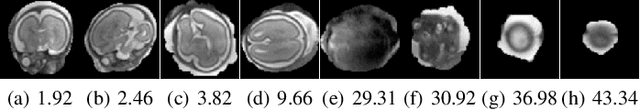

Abstract:In this paper we present a novel method for the correction of motion artifacts that are present in fetal Magnetic Resonance Imaging (MRI) scans of the whole uterus. Contrary to current slice-to-volume registration (SVR) methods, requiring an inflexible anatomical enclosure of a single investigated organ, the proposed patch-to-volume reconstruction (PVR) approach is able to reconstruct a large field of view of non-rigidly deforming structures. It relaxes rigid motion assumptions by introducing a specific amount of redundant information that is exploited with parallelized patch-wise optimization, super-resolution, and automatic outlier rejection. We further describe and provide an efficient parallel implementation of PVR allowing its execution within reasonable time on commercially available graphics processing units (GPU), enabling its use in the clinical practice. We evaluate PVR's computational overhead compared to standard methods and observe improved reconstruction accuracy in presence of affine motion artifacts of approximately 30% compared to conventional SVR in synthetic experiments. Furthermore, we have evaluated our method qualitatively and quantitatively on real fetal MRI data subject to maternal breathing and sudden fetal movements. We evaluate peak-signal-to-noise ratio (PSNR), structural similarity index (SSIM), and cross correlation (CC) with respect to the originally acquired data and provide a method for visual inspection of reconstruction uncertainty. With these experiments we demonstrate successful application of PVR motion compensation to the whole uterus, the human fetus, and the human placenta.